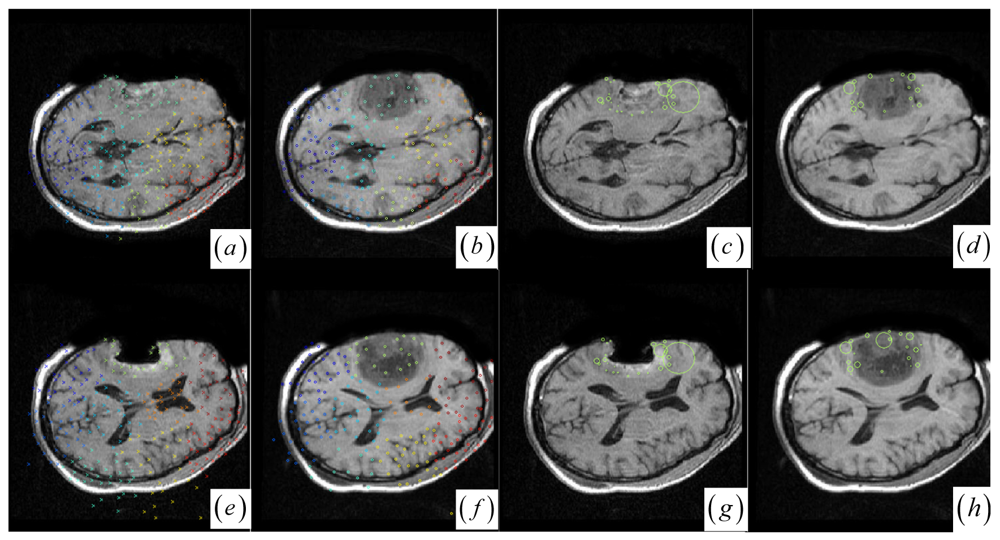

Note that if one cluster pair of tumor regions suffers from the large structural mismatches with local large deformation and outliers, this cluster pair will bring together many keypoints and small average JSM value ζk (computed as ζk = Σw (yi)/card (Ck) (yiCk)). Therefore, the keypoint cluster of tumor region in each image can be localized if its ζk is below a threshold value (ζthreshold = 0.4). In Figure 1j and Figure 2a,b, the keypoint clusters in both images are sorted according to the average JSM values {0.266, 0.404, 0.494, 0.533, 0.560, 0.565, 0.590, 0.639, 0.734}. The tumor resection clusters with ζ1 = 0.266 could be automatically detected from the nine clusters. Figure 2e,f shows that the two images have ten clusters with the tumor resection cluster having 0.234 average JSM value. Furthermore, the keypoint clusters of tumor regions in both images could be regarded as an ellipse model based on the mean and variation of the cluster, and then the outlier keypoints inside the ellipse are removed while the boundary significant keypoints (Figure 2c,d,g,h) are saved for subsequent correspondence detection, i.e., delete x = (x, y) if [ (xμx)2/(κσx)2 + (yμy)2/(κσy)2] < 1 with κ = 0.1. After outlier keypoint rejection, we approach the control point setup and related correspondence detection as follows.

In contrast to four state-of-the-art intensity-based registration methods, including B-Spline with correlation ratio [56] (BCR), B-Spline with normalized MI (BMI) [34, 57], Demons (DEM) [58] and diffeomorphic Demons (DIF) [59], which are failed or unsatisfactory in tumor resection with outliers and local large deformation, our proposed method based on JSM & keypoint clustering (JKC) successfully model the tumor resection-induced brain shift (see Figures 34 and Table 1 cases 1–3). Table 1 summarizes the registration quality in terms of correlation ratio (CR) and normalized MI (NMI) [4, 60]. Figure 3a–d and Figure 4a–d show that the regions around the tumor areas have smoothly deformed to shift towards the tumor resection areas in the JKC registration results. The smoothly constructed deformation field is displayed by means of displacement vector field with variations of the vector color (from blue to red according to the displacement amplitude in pixels). The quality of these registration results also can be validated by the respective small CRs listed in the Table 1 cases 1–3. We also define the average error distance between the manually defined reference landmarks and the floating landmarks in the registered images (Figure 5 shows that most landmarks are around the tumor resection areas and the neighboring normal tissues), our method's average accuracy for the three cases of local large deformation (cases 1–3) achieves an average error distance of less than 1.2 pixel while the average accuracy for the two cases of small deformation achieves an average error distance of less than 1 pixel.

The BCR and BMI registration are implemented at two pass with the different transformation options (B-Spline degree for all axes: 1, 2; B-Spline control points for all axes: 8, 16; gradient descent minimize step size: 1.0, 0.5; gradient descent minimize maximum search steps: 10, 10) and the different iteration options (the convergence limit of minimum change rate for one iteration: 0.1, 0.01; maximum number of iterations: 10, 10) [57]. The dark areas on the deformation image (Figure 3f,h and Figure 4f,h) are related to the areas on the two images which did not perform a deformation during the registration or the deformation was relatively small. The light areas are related to the areas on the two images which perform a bigger deformation. In contrast to the BMI (Figure 3e,f and Figure 4e,f) that fails to compensate the local large deformation around the tumor areas, the BCR (Figure 3g and Figure 4g) can guide the anatomical structure deformation around the tumor resection regions (This also can be validated from the cases 1–3 at Table 1, at which the BCR have smaller CRs than the BMI, DEM and DIF). Nevertheless, the BCR has blurred and excessively shrunk the pre-operative anatomical structures around the tumor areas. From this experiment, we also confirm that the CR is more appropriate to be a similarity measure for the nonrigid monomodal registration of small structures than the NMI.

Figure 2. (a)–(b) and (e)–(f) Clustered significant keypoints in the two images. (c)–(d) and (g)–(h) Boundary significant keypoints around tumor resection regions with circles defining the scale measures of the points.